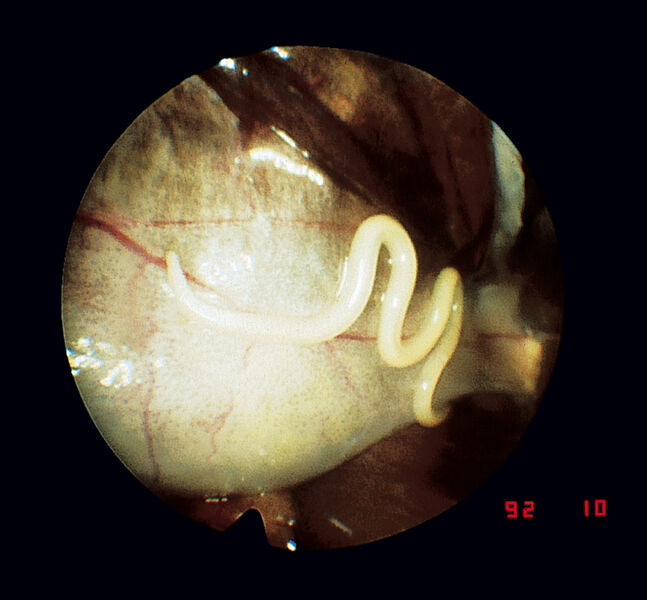

鳥類、両生類、小型ほ乳類、魚類に使用できる汎用内視鏡

- セリオスコピー、総排出腔鏡検査、膀胱鏡検査、鼻鏡検査、耳鏡検査、膣鏡検査、視覚管理下での挿管、口腔検査、性別判定、その他、多くの内視鏡手術や処置を行うことができます。

- 多くの外来動物は小さくて華奢な体格であるため、内視鏡検査は理想的な検査方法です。